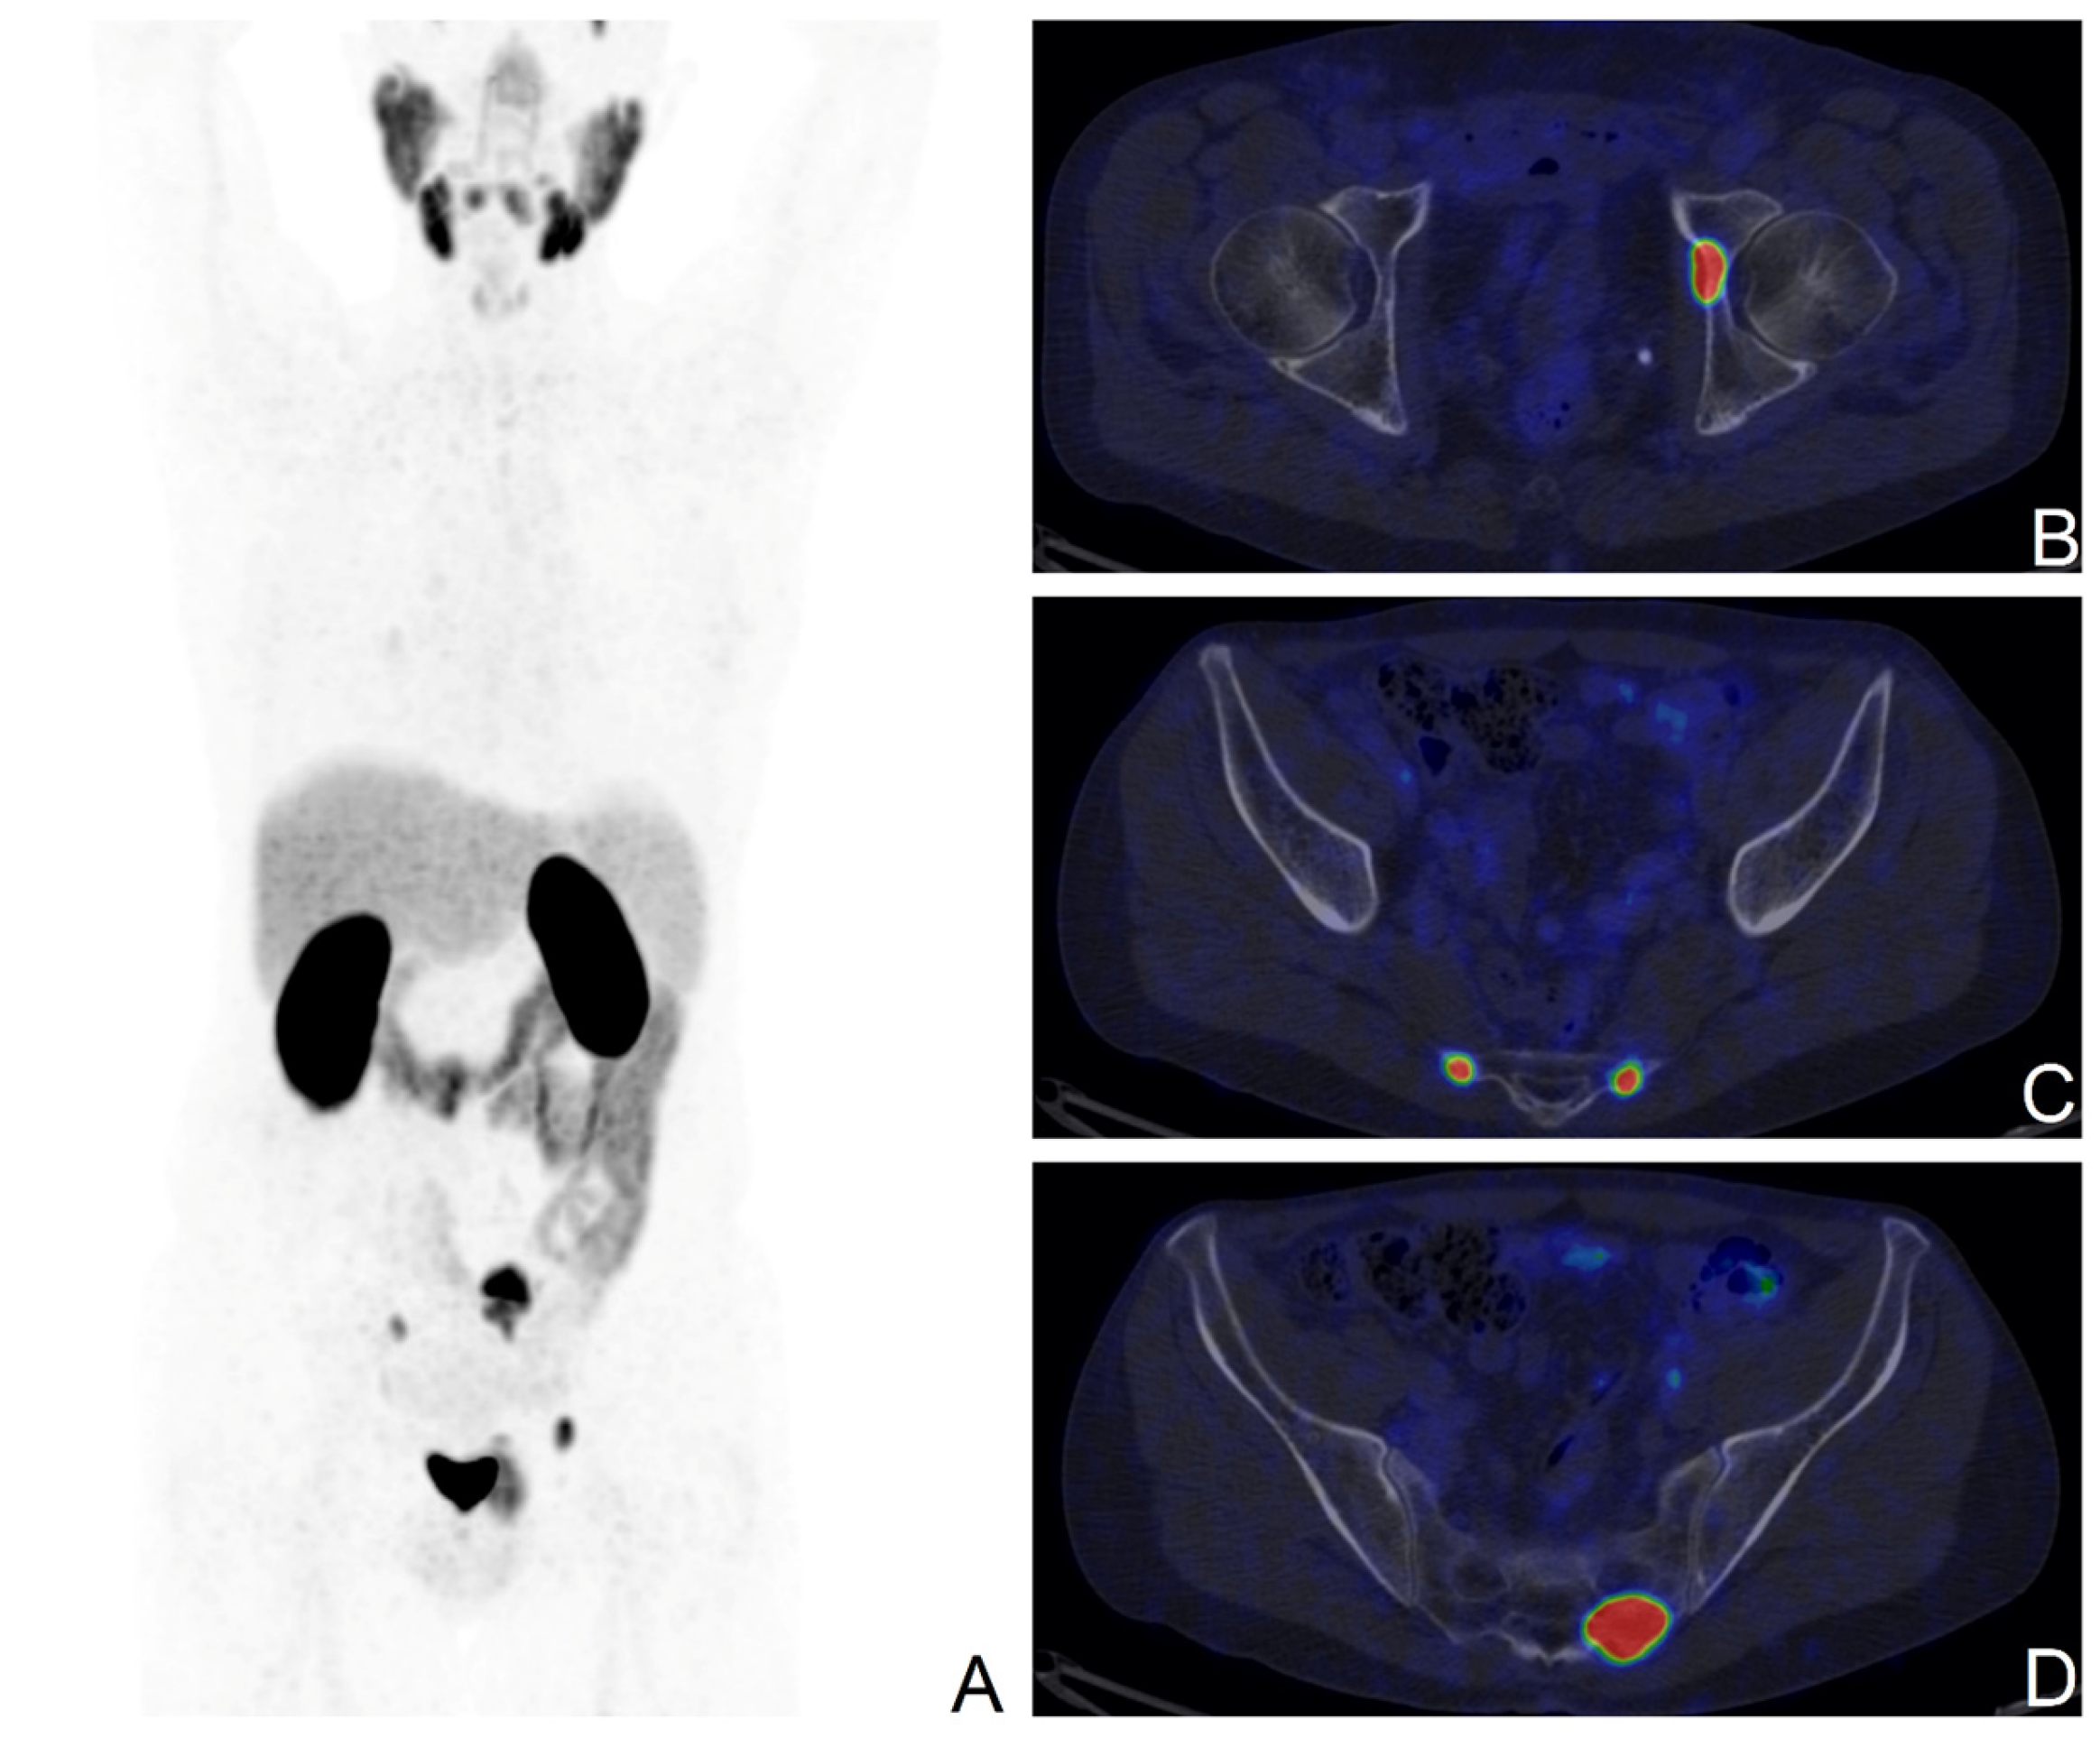

3.2. PET Findings

3.3. Validation of [68Ga]Ga-PSMA-11 PET Findings